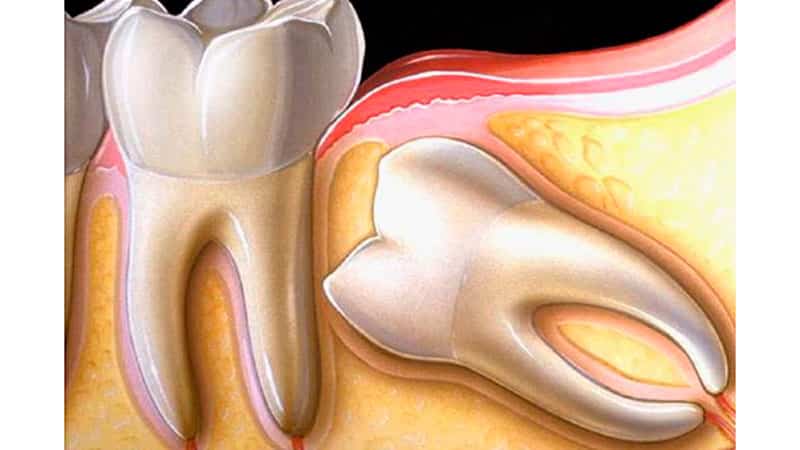

Когда стоматологи упоминают о ретинированном зубе, многие не понимают, что это означает. На самом деле, этот термин используется для обозначения зуба, который не смог прорезаться должным образом. Ретенция делится на два типа:

- частичная (когда видна лишь часть зуба, что указывает на его неполное прорезывание);

- полная (когда снаружи видна только десна или костная ткань).

Часто врачи сталкиваются с наличием обоих этих дефектов одновременно. Наиболее распространено это явление среди зубов мудрости, которые также известны как третьи моляры. Дистопированный ретинированный зуб мудрости, изображение которого представлено ниже, является довольно распространенной проблемой. Он может вызывать такие осложнения, как пародонтоз, периодонтит, кариес и даже воспалительные процессы в полости рта.